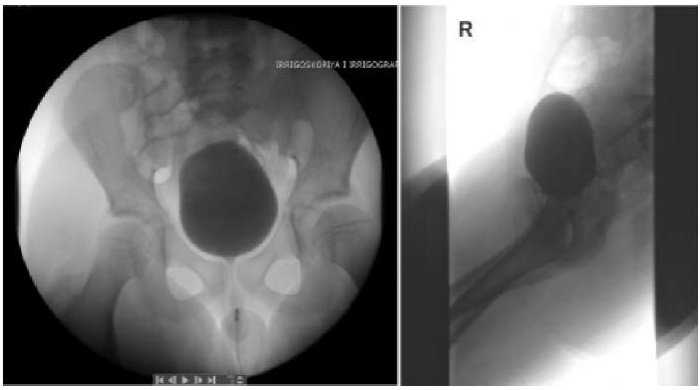

Для визуализации свищевого хода было проведено комплексное обследование. Первостепенно выполнены рентгенологические исследования: цистоуретрография, по данным которой затеков контраста и контрастирования свищевого хода не отмечено (рис. 3). Далее — экскреторная урография, исследование выявило нормальное строение мочевыводящих путей, за исключением незначительного скопления количества контрастного вещества в виде «глыбки» в проекции гребня лобковой кости слева, которое первоначально было расценено как артефакт, но при детальном осмыслении результатов натолкнуло на мысль о связи с мочевым пузырем и предопределило следующее исследование (рис. 4).

Рисунок 3.

Микционная цистуретрография: данных за патологию нижних мочевых путей не отмечается (фото из архива кафедры детской хирургии и урологии — андрологии им. Л.П. Александрова)

Figure 3.

Voiding cystourethrography: no evidence of lower urinary tract pathology (photo from the archive of the L.P. Alexandrov Department of Pediatric Surgery and Urology–Andrology)